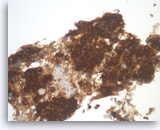

Metastatic adenocarcinoma of the colon,

Pancreas FNA, Cell Block.

The tumor cells are positive for CDX-2 (nuclear staining). This finding along with keratin 20 immunopositivity and the cytomorphologic features supports a colorectal primary.

10X

Metastatic adenocarcinoma of the colon,

Pancreas FNA, Cell Block.

The tumor cells are positive for CDX-2 (nuclear staining). This finding along with keratin 20 immunopositivity and the cytomorphologic features supports a colorectal primary.

10X